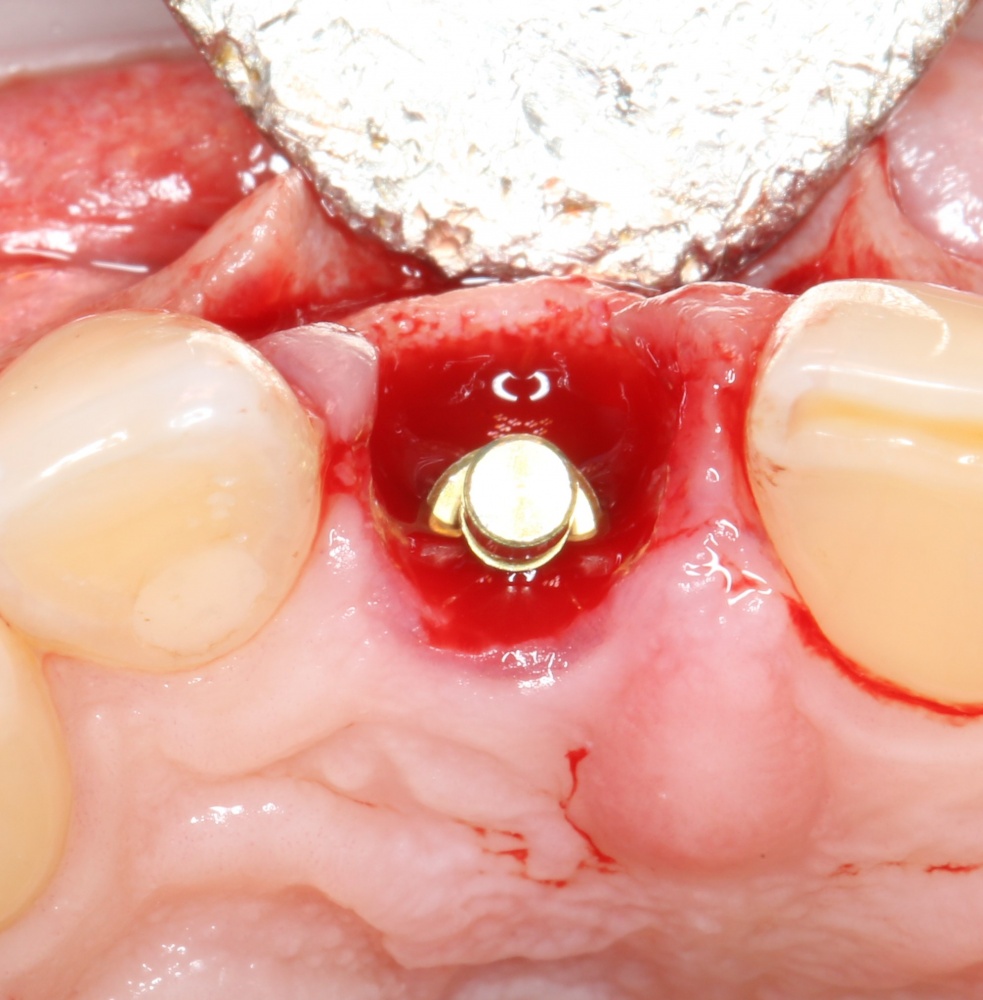

Устанавливается имплантат Astratech (Dentsply Implants):

Для аугментации также используем Bio-Oss Collagen 100 mg, нарезаем его по размеру с помощью скальпеля и позиционируем в лунках щечных корней:

На имплантат ставим формирователь, ушиваем лунку. Напомню, что любой биоматериал должен быть герметично запечатан в ране (фактор успеха III). В противном случае, от него больше вреда, чем пользы: